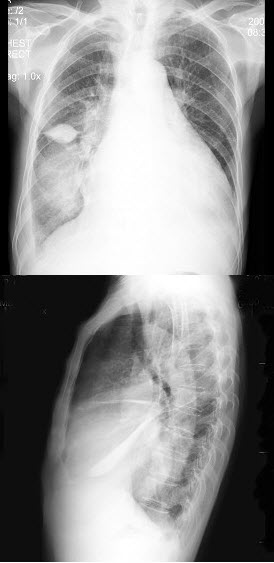

17、单项选择题

女,74岁,胸闷气逼多年,近来加重,X线检查如图,最可能的诊断是()

A.心包积液并右肺肿块

B.心包积液并右肺叶间积液

C.心包积液并右肺炎

D.心包积液并右侧胸膜肥厚

E.以上都不对